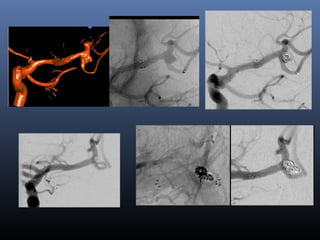

17 patients: SS, ODS, SS+Coil

1 rebleed (died)

Good outcome on f/u – 82%

Mortality – 18%

Blister Aneurysm

Our experience with FD vs non FD

Complete occlusion – 89% vs 71% i.f.o FD

Repeat treatment – none vs 11.7% i.f.o FD

Rebleed resulting in death – none vs 5.8% i.f.o FD

Submitted for publication

Learning points

• FD was safe and effective in these aneurysms and

compared favorably with our previously reported results

with stent(single/overlapping) and coiling

• In our series loading with Pasugrel and ecospirin was

safe and effective for flow diverter placement in acutely

ruptured blister aneurysms

Antiplatelet protocol: 2 hrs prior to stent

deployment

Ecosprin 150 mg & Prasugrel 50 mg

Heparin 3000 IU at start of procedure

1000 IU to 2000 IU prior to stent deployment

ACT 300 (x 2 upper limit of normal)